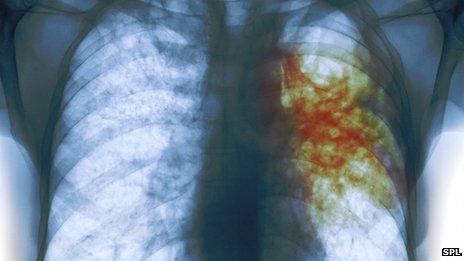

'Wrong' immune response aids TB

Some bacteria, including tuberculosis, are able to invade because the body launches the 'wrong' immune response, say researchers.

Instead of fighting off tuberculosis, people with a severe infection produce a protein which attacks viruses, the journal Science reports.